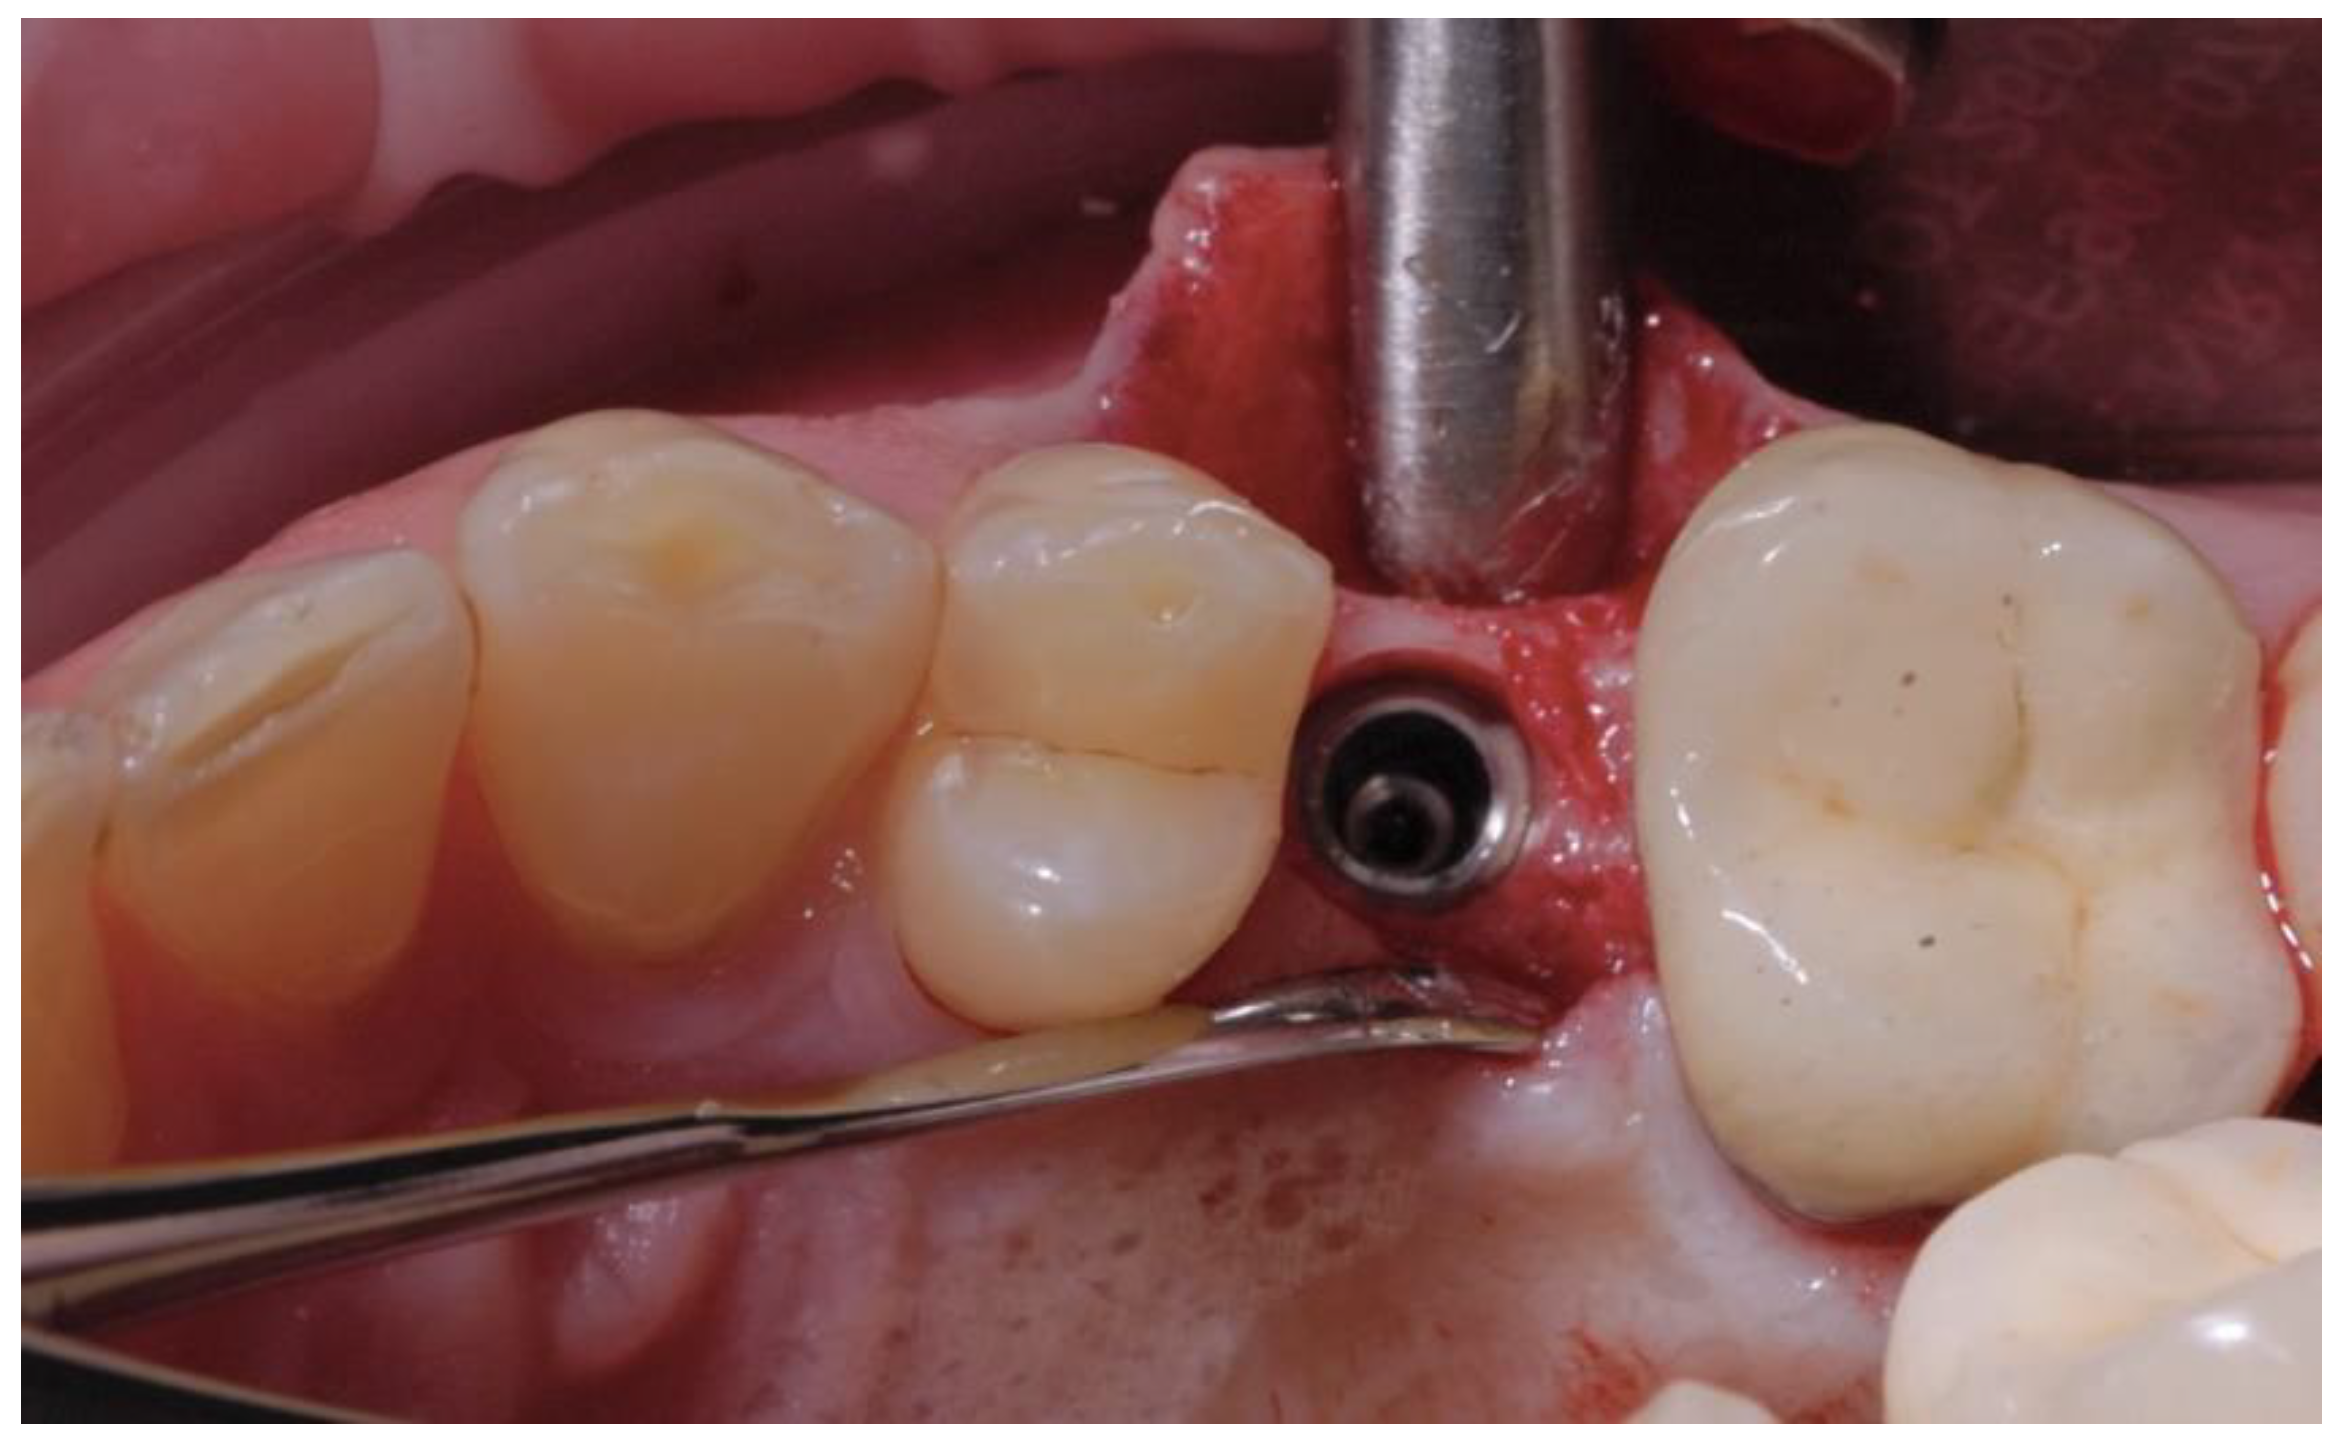

2.2. Surgical Procedures